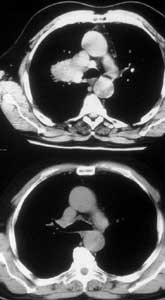

This technique is very versatile and can be used in a variety of circumstances. These range from limited infiltration involving the origin of segmental arteries to large defects extended longitudinally on the PA (Figures 8, 9). The only necessary condition is that the opposite side of the circumference of the PA is free from tumor.

![]() |

| Figure 9: Line drawing (left) and intraoperative image (right) showing the usual pattern of infiltration of the interlobar portion of the pulmonary artery posterior to the left upper lobe bronchus.* | |